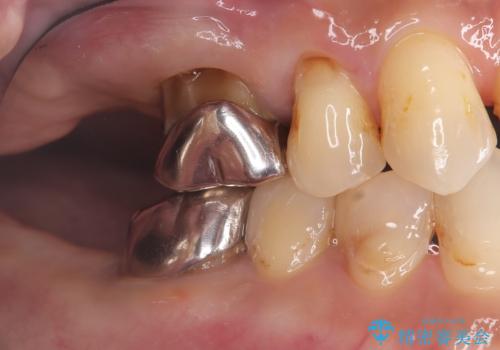

- 治療計画

- 患者様は、右側の奥歯でしっかり噛めないことを主訴に来院されました。診察の結果、右上6・右下6の根管治療が不十分で、感染のリスクがある状態と判断。これらの歯は再根管治療を行い、セラミッククラウンで補綴することにしました。また、右上7・右下7は欠損しており、噛み合わせを回復するためにインプラント治療を計画しました。